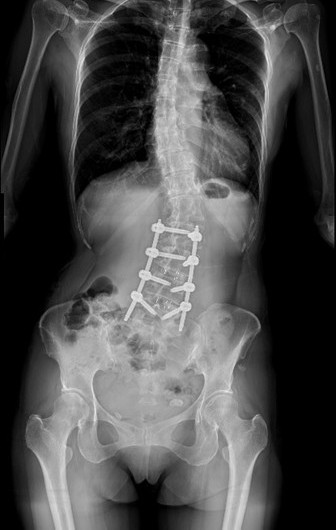

55歲的黃小姐,年輕時曾被醫師提醒脊椎側彎,多年來不以為意,直到近兩年伴隨脊椎劇痛、下肢麻痺與腫脹,夜晚經常因疼痛而失眠,甚至舉步維艱,已影響工作與生活品質。經友人推薦至臺中市立老人復健綜合醫院骨科就醫,由微創脊椎中心助理副院長張建鈞醫師評估後,決定接受3D導航微創矯正手術,術後從47度矯正至10度,身高增加約5公分,25年的宿疾大幅改善,終能穩入睡。

張建鈞指出,患者因長期未治療,脊椎側彎角度已達48度,屬中重度退化性脊椎側彎,加上合併二尖瓣膜脫垂心臟病史,進行傳統開放式手術風險極高。經完整影像評估與跨科討論後,醫療團隊建議採取「微創前開3D導航矯正手術」,在不大幅破壞背部肌群的情況下,從側邊小切口進行矯正與支撐重建。手術後恢復快速,術後4至5天即順利出院,疼痛明顯減輕。黃小姐笑說,術後穿著背架反而帶來前所未有的安全感,甚至捨不得太快卸除。